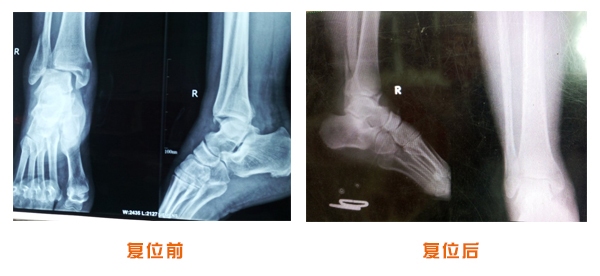

前后對比

踝關節脫位骨折治療前后對比